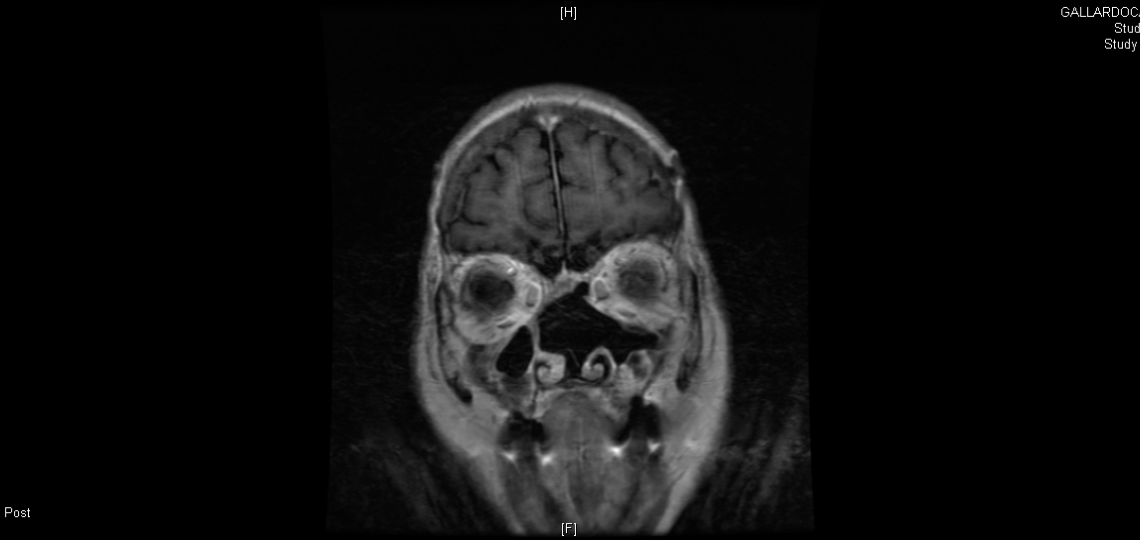

Nose and Sinus Tumors

Tumors in the nose and sinus are close to important structures including the eye, the brain, major nerves and arteries. Treatments for cancers in this area need to target the tumor and still preserve function. Each approach, whether it is a combination of surgery, radiation or chemotherapy, is designed to return the patient to their preoperative functioning and lifestyle while achieving the best possible outcome.